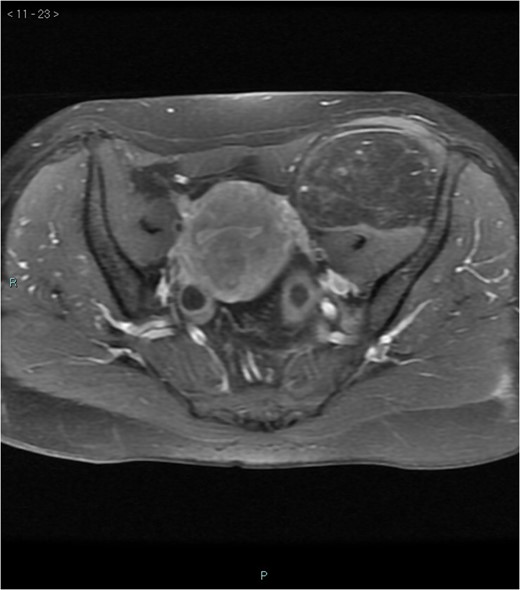

A 58-year-old woman was evaluated for lower abdominal pain, without additional symptoms. An abdominal ultrasonography revealed the presence of a 15 cm homogenous mass, located in the left pelvic cavity. Subsequent MRI showed a capsulated mass, isointense with the adipose tissue, longitudinally extending from the left inguinal area to the left leg root and located on the medial aspect of the left iliac bone. MRI also revealed within the mass some fibrotic branches containing small blood vessels. No evidence of extracapsular invasion of the surrounding structures was evident (Figs 1–6).

Preoperative differential diagnosis is mainly based on radiologic imaging and is very difficult, because no pathognomonic signs exists for diagnosis of hibernoma; usually CT-scan shows an homogenous lesion, whose density is between subcutaneous fat and skeletal muscle; MRI shows slightly lower signal intensity on T1 weighted spin-echo (T1WSE), marked enhancement and partial fat suppression on short Tau inversion recovery (STIR) and fat-saturated sequences [5].